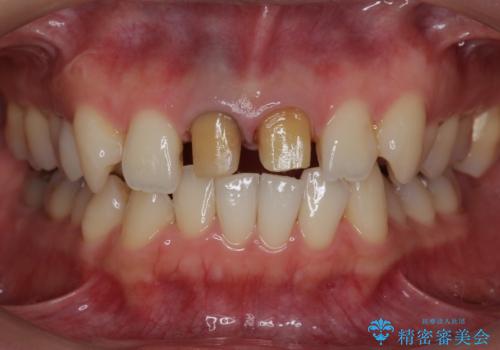

神経をとった前歯が変色してきた

- 昔に神経をとった前歯の変色が気になるとのことでした。

神経の方は問題なさそうだったため、患者様の希望でやりなおさず、土台とセラミック治療を行いました。